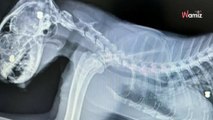

Il nourrit les chats errants du quartier : les marques sur le corps d'un matou révèlent un passé sombre

À la fin du mois de décembre 2023, un chat noir et blanc a été retrouvé en train d'errer dans la rue en Angleterre par un bénévole du Stray Cat Club.